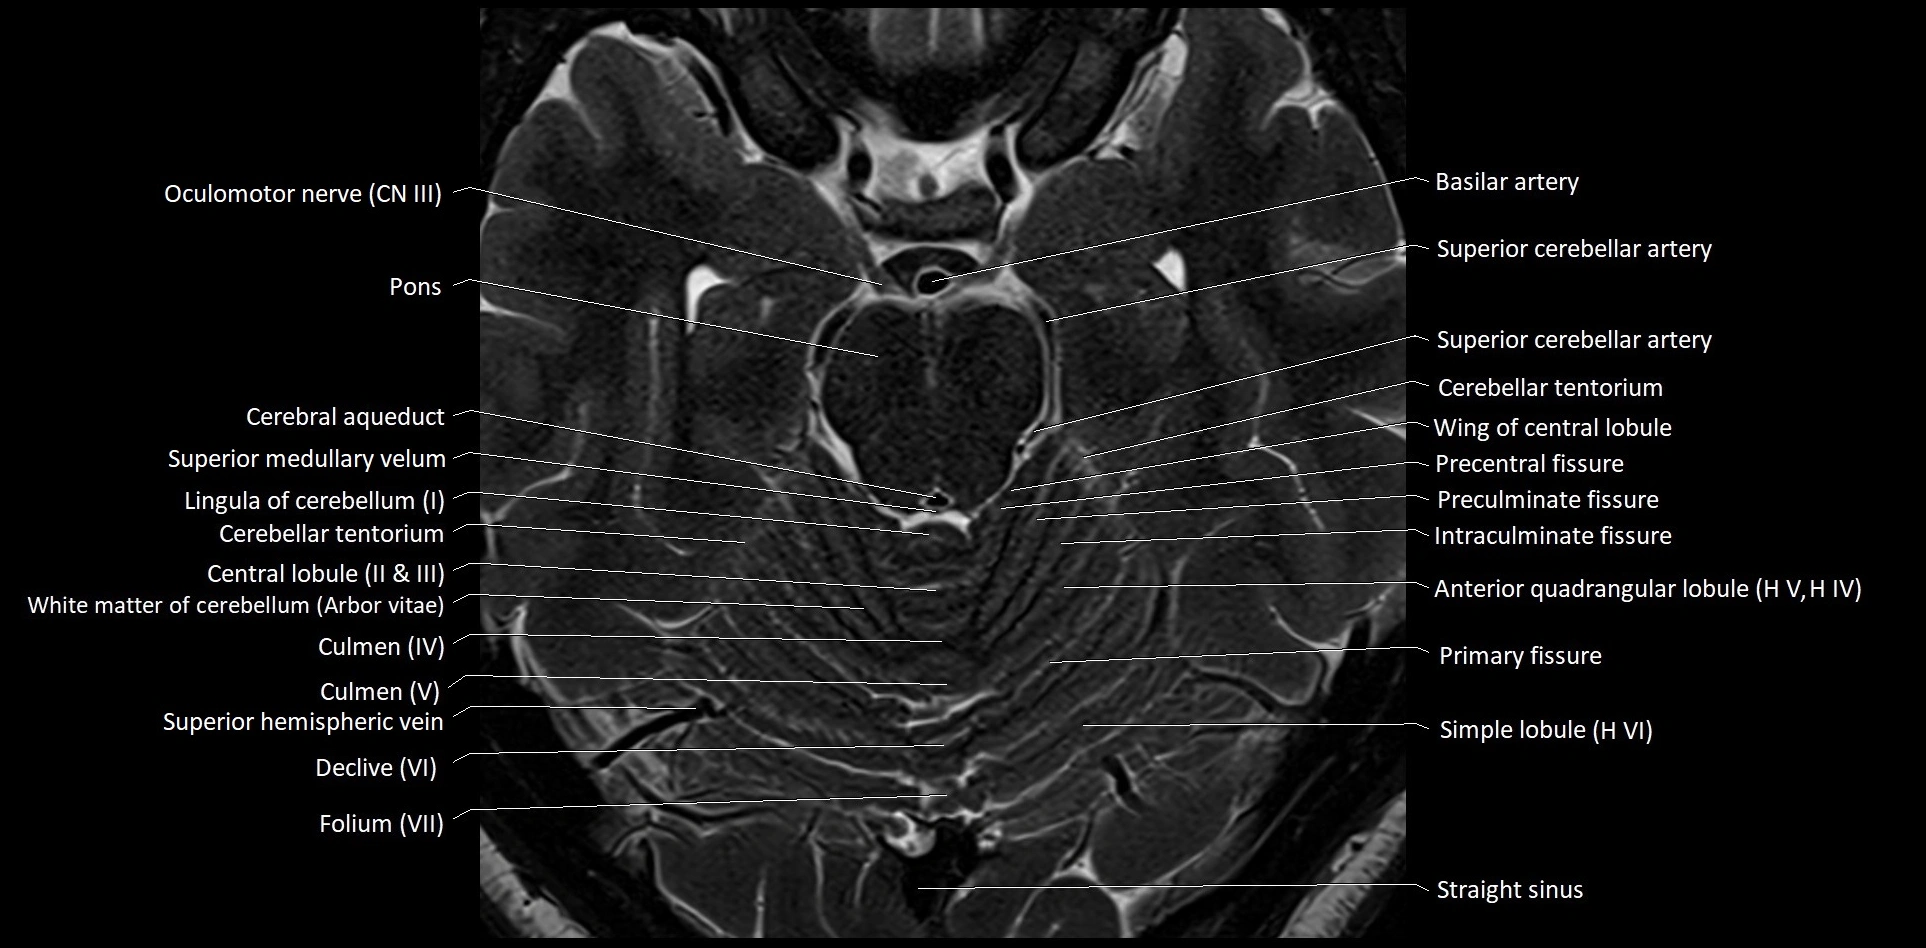

- Cerebellar tentorium

- Culmen

- Culmen (IV, V) of Cerebellum

- Declive

- Declive (VI) of Cerebellum

- Folium (VII) of Cerebellum

- Folium of Vermis

- Intraculminate fissure

- Lingula of cerebellum (I)

- Oculomotor Nerve (Cranial Nerve III)

- Pontine artery

- Precentral fissure

- Preculminate fissure

- Primary fissure

- Simple lobule

- Simple lobule (HVI) of cerebellum

- Straight sinus

- Superior medullary velum

- Wing of central lobule